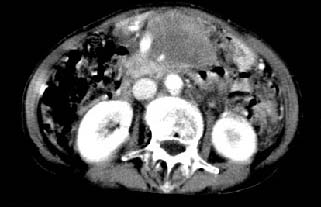

女:61岁.腹痛腹胀20天,行b超腹膜后实性占位.扫完后我查体发现患者右颈根部约3厘米类圆性包块,有移动{我考虑右颈根部包块是肿大淋巴结}.

ct:肝胃之间、胰头后、腹主a周围,融合而成团块状影,包绕血管,胰腺前移后缘分界欠清,与肝胃分界清,肿块未见明显强化,肝右叶后段小囊肿。

女:61岁.腹痛腹胀20天,行b超腹膜后实性占位.扫完后我查体发现患者右颈根部约3厘米类圆性包块,有移动{考虑右颈根部包块是肿大淋巴结}.

诊断:淋巴瘤>转移瘤。

肝胃之间、肝十二指肠韧带,胰头后、腹主a周围,融合而成团块状影,包绕血管[腹腔干、肠系膜上动脉,腹主动脉],胰腺前移后缘分界欠清,与肝胃分界清,肿块未见明显强化,肝右叶后段小囊肿。

主动脉-胰腺间隙可见巨大分叶状软组织肿块影,包绕腹主动脉、腹腔干及其分支、腔静脉等大血管,增强呈无明显强化,临近脏器明显受压移位,增强示有分界。肝右叶可见局限性低密影,边缘清楚。

考虑腹膜后淋巴瘤。